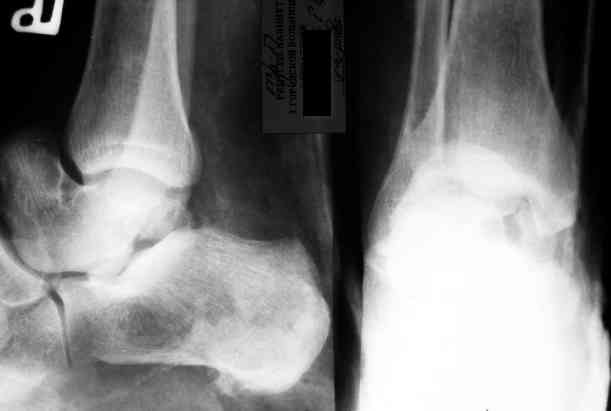

Уважаемый Александр! Как обещал представляю Р-граммы и операционные фото.

Опять надоедаю с вопросами:

Ваши (лично ваши) рекомендации - астрагалэктомия-аппаратный пяточно-большеберцовый артродез с одновременным удлинением голени - правильно?

Можно убрать таранную кость, и поместить в образовавшуюся полость либо бусы из цемента с антибиотиками, либо вылепленный прямо по форме тарана спейсер. Целесообразность этого будет определяться распространенностью гнойного процесса. Может быть, будет достаточно только удаления тарана.

Вместе с аваскулярным куском кости устранится субстрат. Надо опасаться не мягких тканей, а плохо кровоснабжаемых. Если после удаления тарана добиться контакта хорошо васкуляризованных пятки и больщшеберцовой, мягкие ткани не давить, чтобы некроза раны не было, то все должно зажить.